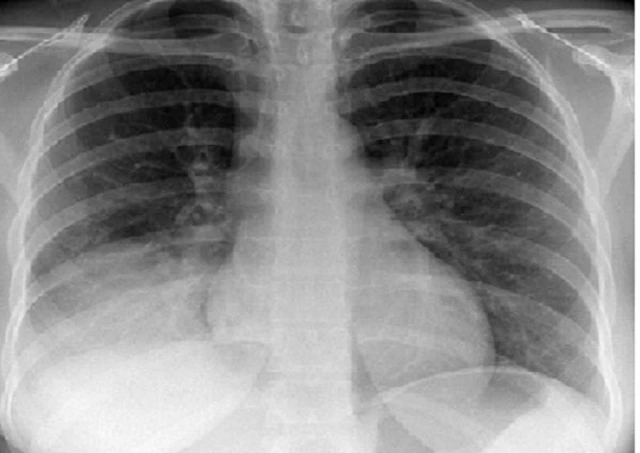

Khi một cơ quan nào trong cơ thể xảy ra vấn đề thì đều gây ảnh hưởng đến sức khỏe, đặc biệt khi cơ quan đó là phổi. Đóng vai trò quyết định trong việc trao đổi khí giữa cơ thể và môi trường bên ngoài, phổi thường xuyên tiếp xúc với các tác nhân lạ nên khả năng cao bị bệnh lý gây tác động đến hệ hô hấp. Một trong số những bệnh nguy hiểm và đáng chú ý là xẹp phổi với tỷ lệ ngày càng gia tăng. Xẹp phổi là căn bệnh liên quan đến đường hô hấp với các biến chứng nguy hiểm, thậm chí đe dọa tính mạng nếu không được điều trị kịp thời. Hãy cùng Long Châu tìm hiểu nguyên nhân, triệu chứng, chẩn đoán và điều trị xẹp phổi sẽ giúp bạn tự bảo vệ bản thân và có biện pháp phòng tránh thích hợp.